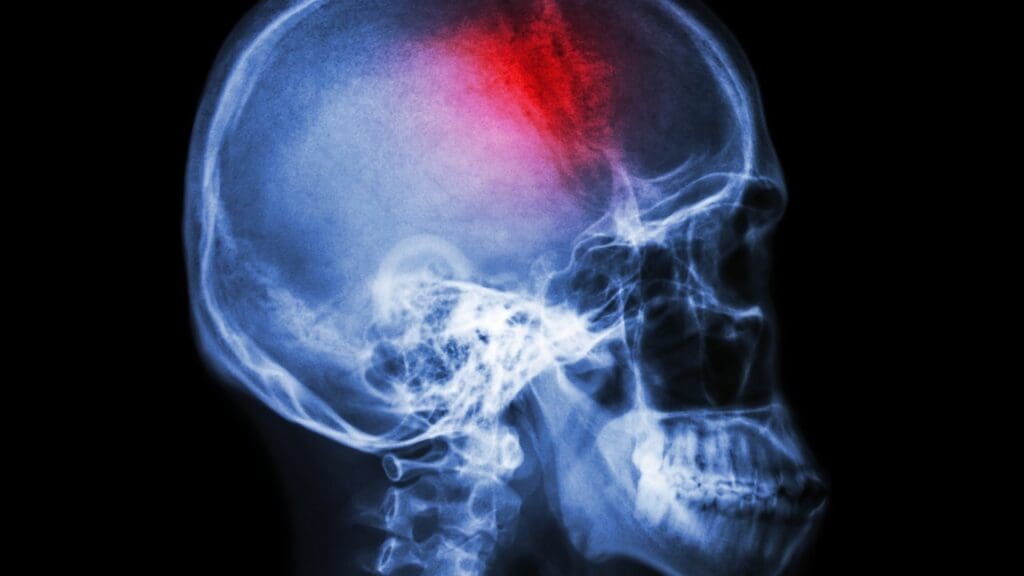

A lesion in the brain is damaged brain tissue. It can happen from infections, trauma, or vascular diseases. We spot these lesions with neuroimaging techniques like MRI and CT scans.

Neuroimaging is key in finding brain lesions. MRI, CT, and PET scans give us clear brain images. They help us see where, how big, and what kind of lesions are there.